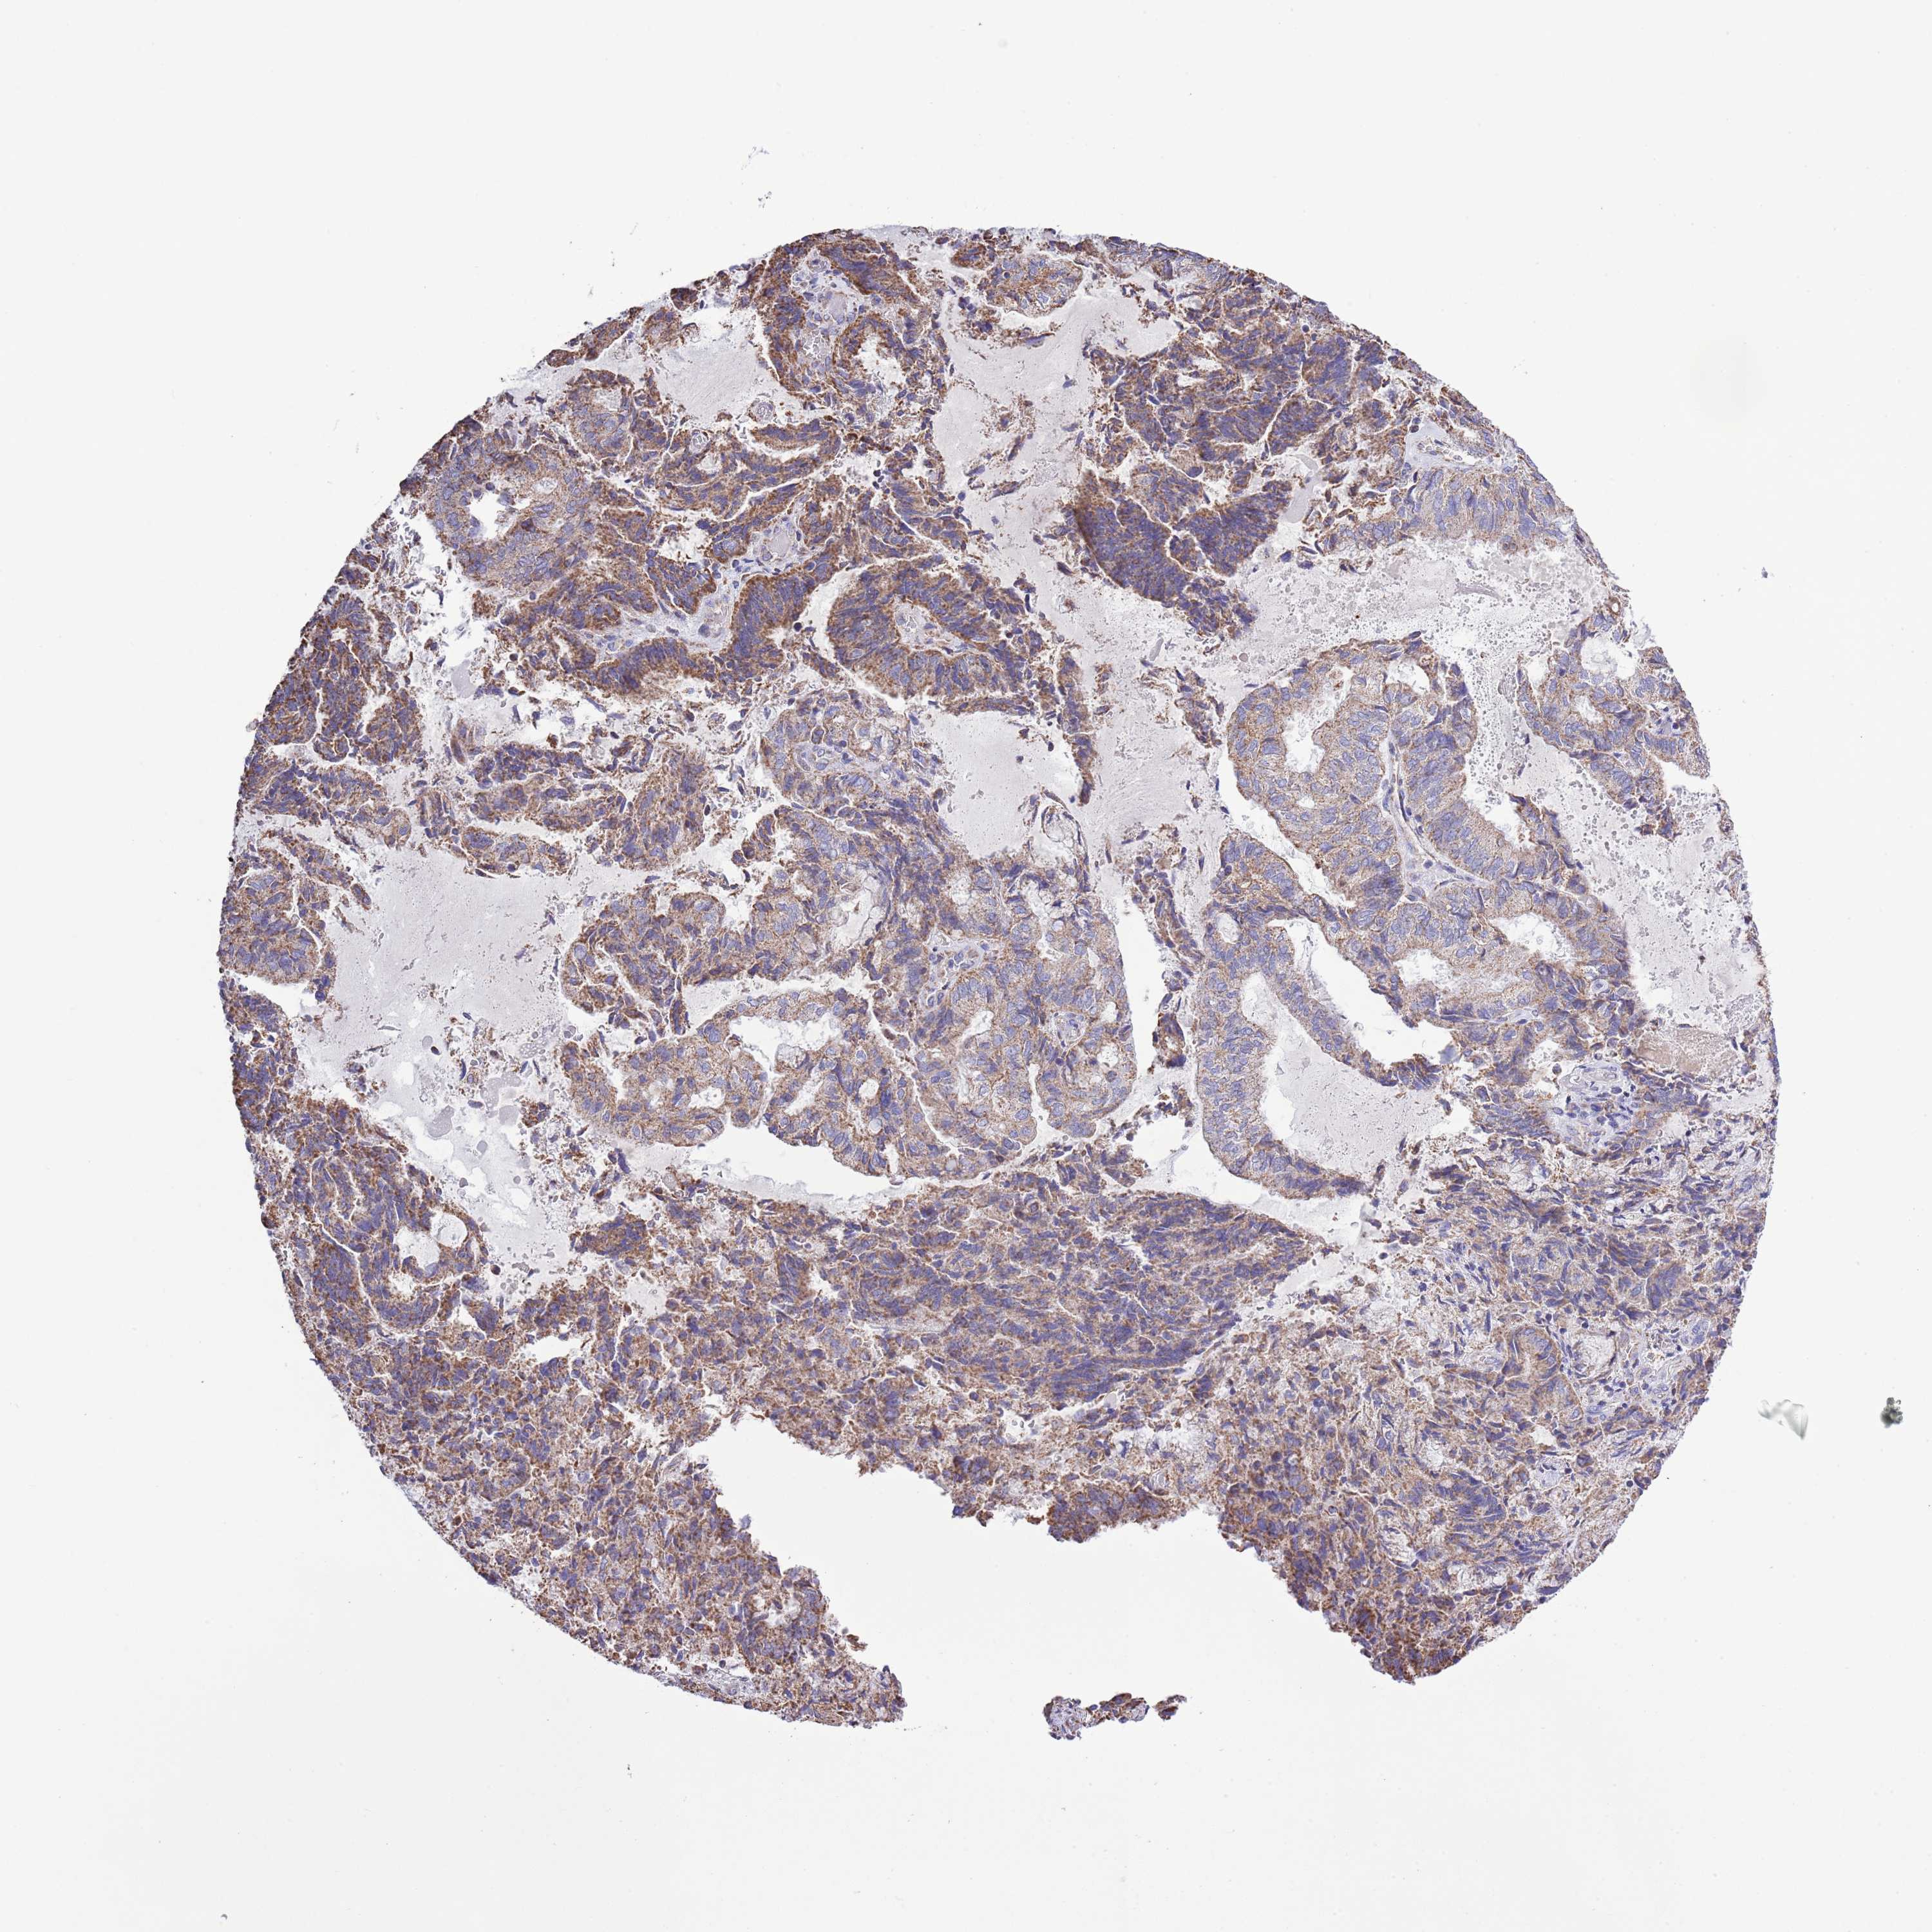

ENDOMETRIAL CANCER - Protein expressioni

A mouse-over function shows sample information and annotation data. Click on an image to view it in a full screen mode. Samples can be filtered based on level of antibody staining by selecting one or several of the following categories: high, medium, low and not detected. The assay and annotation is described here.

Note that samples used for immunohistochemistry by the Human Protein Atlas do not correspond to samples in the TCGA dataset.

Antibody stainingi

Antibody staining in the annotated cell types in the current human tissue is reported as not detected, low, medium, or high, based on conventional immunohistochemistry profiling in selected tissues. This score is based on the combination of the staining intensity and fraction of stained cells.

Each image is clickable and will lead to virtual microscopy that enables deeper exploration of all samples and also displays staining intensity scores, fraction scores and subcellular localization as well as patient and tissue information for each sample.

Antibody HPA048654

Staining

High

Medium

Low

Not detected

Intensity

Strong

Moderate

Weak

Negative

Quantity

>75%

75%-25%

<25%

None

Location

Nuclear

Cytoplasmic/membranous

Cytoplasmic/membranous,nuclear

Adenocarcinoma, NOS